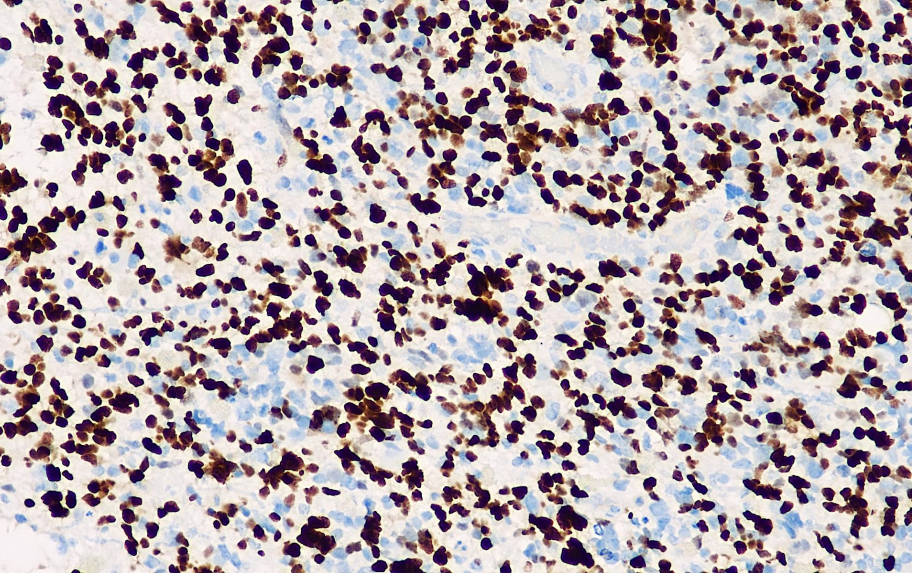

Positive control: oligodendroglioma

Expressed in normal oligodendrocytes as well as tumorigenic oligodendrocytes, with the nucleus as the site of positivity. Tumorigenic astrocytes can also be positively expressed, but with lighter coloring than oligodendrocytes. Mainly used in the diagnosis of oligodendrocyte tumors.

Olig2 antibody reagents can specifically bind to Olig2 molecular antigens. Immunohistochemical kits containing Olig2 antibody reagents are suitable for the precise diagnosis of oligodendrocyte tumors.